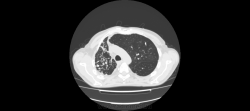

Здравствуйте, уважаемые коллеги! Меня зовут Владимир, работаю рентгенологом в ПТД, с недавнего времени осваиваю КТ. Хочу спросить вашего мнения по исследованию.

Больной наблюдается в ПТД с 2008го года. МБТ+ ни разу не было. На данный момент на фоне не специфической терапии отмечается снижение температуры, соэ остается высоким (60). Данные рентгенархива, к сожалению опубликовать не могу-нет фотоаппарата. Поэтому выкладываю сканы и видео.

Правое легкое уменьшено в объеме - значит есть фиброз, имеются полости распада - значит есть каверноз. А вот есть ли туберкуллез. Нет ВК, и локализация не вполне типична - в нижней доле. Может другой, столь же агрессивный возбудитель; например, актиномиккоз. Тема для консультации в вышестоящем ЛПУ.

Да, "неправильный" какой-то туберкулез. При таком массивном поражении одного легкого второе оказывается практически здоровым? Во всяком случае, своим неКТшным взглядом явной патологии не нашел. К тому же отсутствие ВК, и это при таких "кавернах"? Надо искать что-то другое, во всяком случае исключать. На вскидку даже трудно предложить дифряд. Что-нибудь грибково-простейшее?

Можно даже предположить, что первично был вариант или аномалия развития легкого, что-то связанное с врожденными кистами, гипоплазией и прочим.

Огромное спасибо за комментарии! Мне почему-то тоже пришла мысль о порочно развитом легком и присоединившейся позже инфекции, переросшей во временами обостряющийся хронический процесс.

Т.е. с Вашей точки зрения, процесс больше тянет на неспецифический?